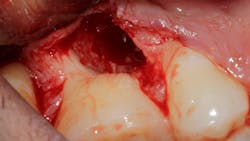

Saving compromised multirooted teeth with root amputation can often be successful, but the technique is sensitive and complex. Proper case selection is essential, and considerations include the following:

There is sufficient bone support around the remaining roots (at least 50% or more is needed) along with sufficient coronal tooth structure (figure 3).How does root amputation compare with other surgical procedures?